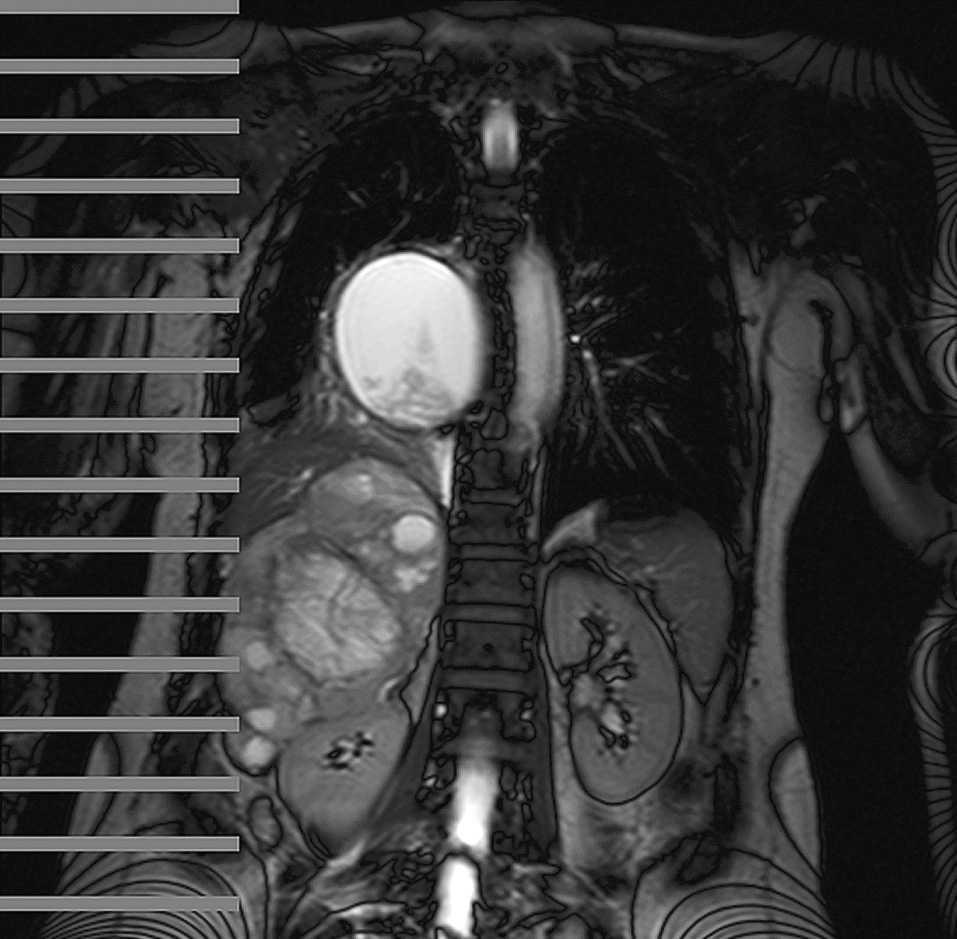

Fig. 1.

Paciente de 56 años con historia previa de hipertensión, diaforesis y palpitaciones de 5 años de evolución. Ingresa en nuestro hospital por cuadro de crisis hipertensiva, tos y disnea. En la exploración abdominal, destaca una masa palpable en el hipocondrio derecho. Se realiza resonancia magnética toracoabdominal que muestra una tumoración mediastínica de 9 × 9 × 7 cm que provoca desplazamiento de la aurícula izquierda, el esófago y la vena pulmonar derecha, acompañado de colapso pulmonar derecho. Además, se observa una masa suprarrenal derecha de 16 × 12 × 8,5 cm que desplaza el lóbulo hepático derecho y el riñón derecho. El estudio se completa con tomografía computarizada por emisión de fotones simples con metayodobenzilguanidina marcada con 131I y octeótrido, y tomografía por emisión de positrones con fluorodesoxiglucosa F18, las cuales muestran la captación patológica únicamente de la tumoración suprarrenal derecha. En el análisis bioquímico destaca la elevación de las catecolaminas y metanefrinas en plasma y orina. Se realiza laparotomía subcostal derecha y exéresis de tumoración en la tumoración suprarrenal. En el postoperatorio la paciente se mantuvo normotensa sin medicación antihipertensiva. A la sexta semana de la intervención se realizó toracotomía posterolateral y exéresis del quiste mediastínico. La anatomía patológica confirmó el diagnóstico de feocromocitoma y puso de manifiesto que la tumoración mediastínica se trataba de un quiste benigno.

Diagnóstico: Feocromocitoma y quiste benigno mediastínico.